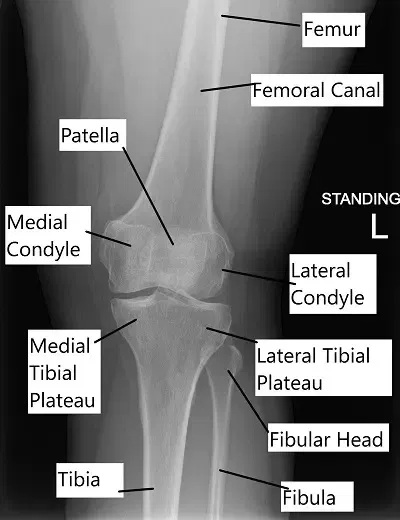

Radiografía que muestra anatomía de rodilla.